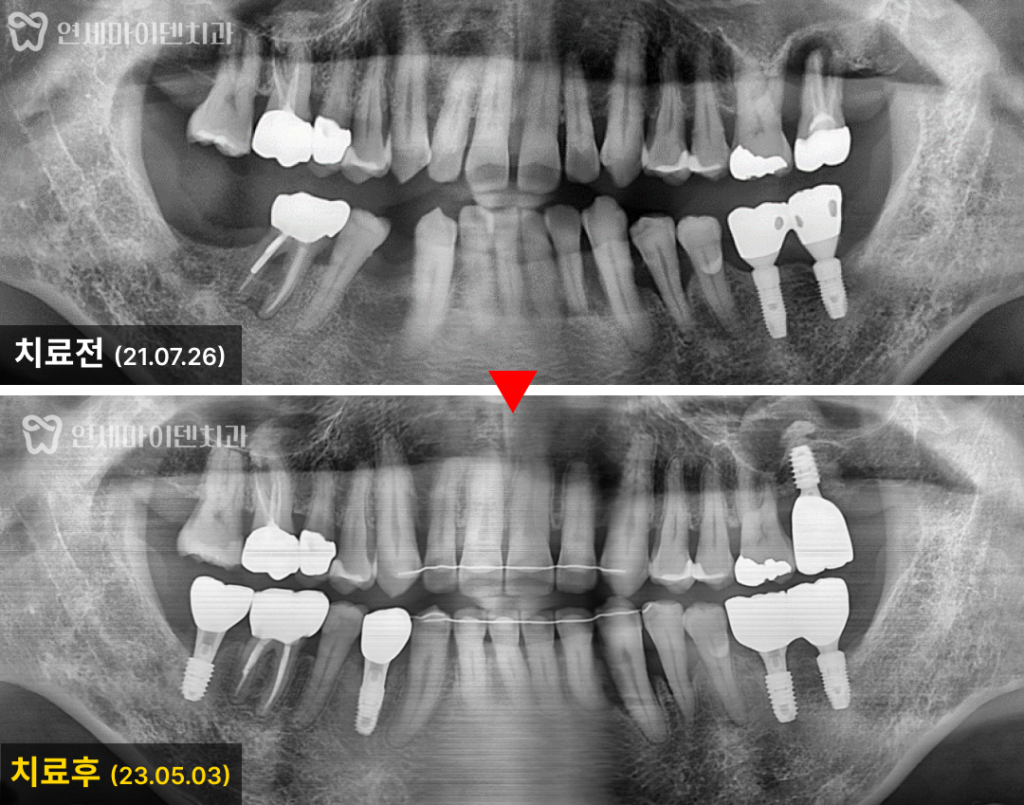

환자분은 교정 장치를 장착한 후

약 9개월 정도 치아 교정을 먼저 시작했습니다.

그 결과, 처음에 벌어져 있던 앞니 사이의 공간이

안정적으로 닫힌 것을 볼 수 있습니다.

아랫니 역시 많이 쓰러져 있던 치아들이

똑바로 세워져 임플란트 식립 공간을 확보했습니다.

이후 교정 시작 약 1년 6개월 만에

임플란트 식립과 치아 교정까지 마무리 하였습니다.

치열은 가지런하게 정리되었고, 처음 진단 때와 비교하면

눈에 띄게 달라진 모습을 확인할 수 있습니다.